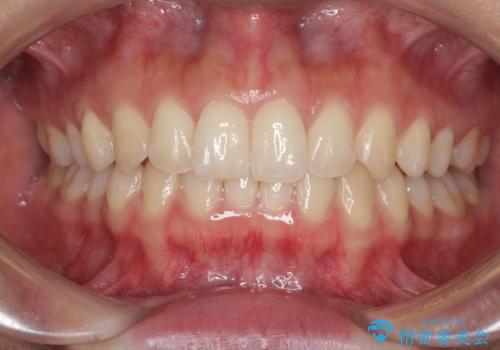

- 深い咬み合わせ(ディープバイト)と前歯のデコボコを気にして来院された患者様です。

インビザラインによる上下歯列の側方拡大と後方移動、IPR(歯と歯の間を削る)にるスペースの獲得により、デコボコとディープバイトを改善することとしました。

1日22時間の装着時間をしっかり守ってくださったので、予定通り1年で治療を終えることができました。

ディープバイトによる食いしばり癖も解消され、患者様には大変満足していただきました。